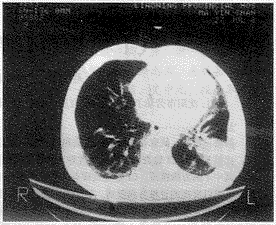

患者接触石棉25年(1954~1979年)

图4 右肺背侧胸膜下肺纤维化(呈曲线状),左肺

大阴影疑似肺癌,酷似圆形肺不张

1.2.2 肺实质改变:在X线胸片上观察到大阴影3例,共3个大阴影,其中1例疑为左侧肺癌。CT检查时,发现4例,5个大阴影,其中1例在右下叶尖段脊椎旁4cm×2.5cm的大阴影,在X线胸片上却未观察到;另1例右肺后下部有炎症阴影,在X线胸片上也未显示。此外,CT检查显示的蜂窝状影、胸膜下曲线状肺纤维化影,左侧大阴影疑为肺癌,但未经组织学证实,其形态酷似圆形肺不张(图4)。纵隔胸膜粘连及心包胸膜粘连各1例,这些所见均可补充X线胸片所见之不足。